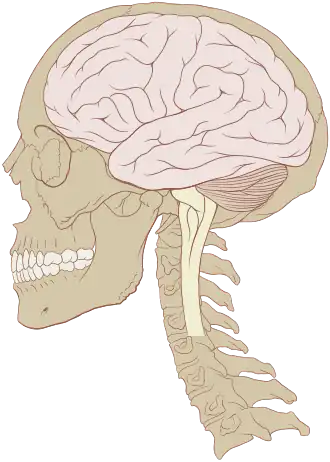

![]() Human brain and skull | |

The human brain is the central organ of the nervous system, and with the spinal cord, comprises the central nervous system. It consists of the cerebrum, the brainstem and the cerebellum. The brain controls most of the activities of the body, processing, integrating, and coordinating the information it receives from the sensory nervous system. The brain integrates sensory information and coordinates instructions sent to the rest of the body.

The adult human brain weighs on average about 1.2–1.4 kg (2.6–3.1 lb) which is about 2% of the total body weight,[2][3] with a volume of around 1260 cm3 in men and 1130 cm3 in women.[4] There is substantial individual variation,[4] with the standard reference range for men being 1,180–1,620 g (2.60–3.57 lb)[5] and for women 1,030–1,400 g (2.27–3.09 lb).[6]

The cerebrum, consisting of the cerebral hemispheres, forms the largest part of the brain and overlies the other brain structures.[7] The outer region of the hemispheres, the cerebral cortex, is grey matter, consisting of cortical layers of neurons. Each hemisphere is divided into four main lobes – the frontal lobe, parietal lobe, temporal lobe, and occipital lobe.[8] Three other lobes are included by some sources which are a central lobe, a limbic lobe, and an insular lobe.[9] The central lobe comprises the precentral gyrus and the postcentral gyrus and is included since it forms a distinct functional role.[9][10]

The brainstem, resembling a stalk, attaches to and leaves the cerebrum at the start of the midbrain area. The brainstem includes the midbrain, the pons, and the medulla oblongata. Behind the brainstem is the cerebellum (Latin: little brain).[7]

The brainstem lies beneath the cerebrum and consists of the midbrain, pons and medulla. It lies in the back part of the skull, resting on the part of the base known as the clivus, and ends at the foramen magnum, a large opening in the occipital bone. The brainstem continues below this as the spinal cord,[38] protected by the vertebral column.